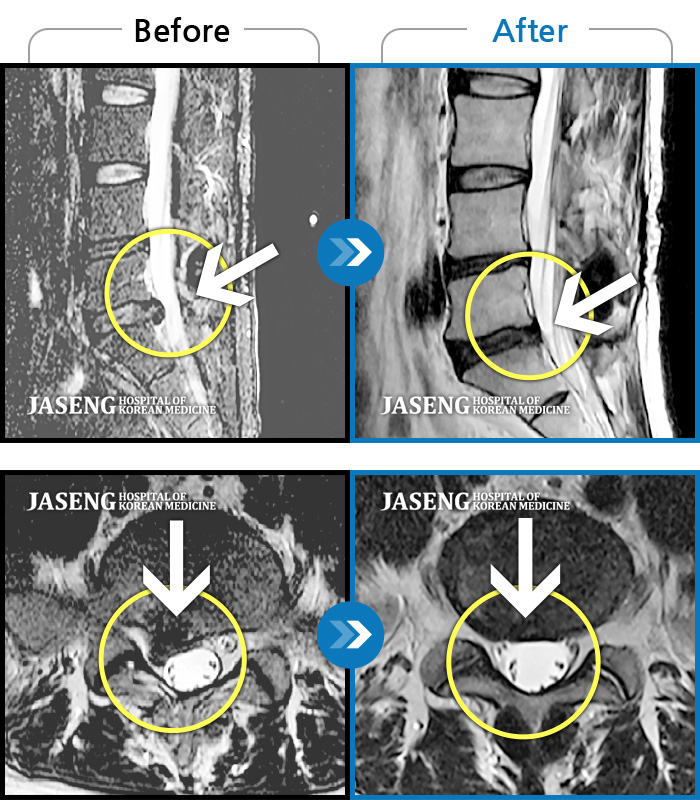

MRI 치료사례

허리에서 다리까지 통증